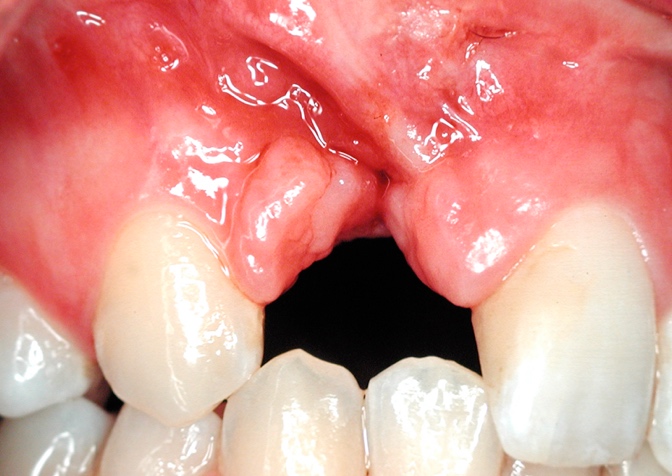

Sequelae of the facial clefts affect the craniofacial complex as a whole. The inter-maxillary relationships are affected by the growth disorders induced by the malformation itself and subsequent deformities, which are largely caused by the scar tissue-related inhibitions that inevitably primary surgery has produced (Fig. 1). This scar tissue intervenes in areas of sensitive growth: the alveolar bone and the supporting tissues of the teeth, the palate, the base of the nose, the soft tissues, etc.

Fig 1 Scar tissue : left, cleft of the lip and palate ; right, isoéated cleft of the palate